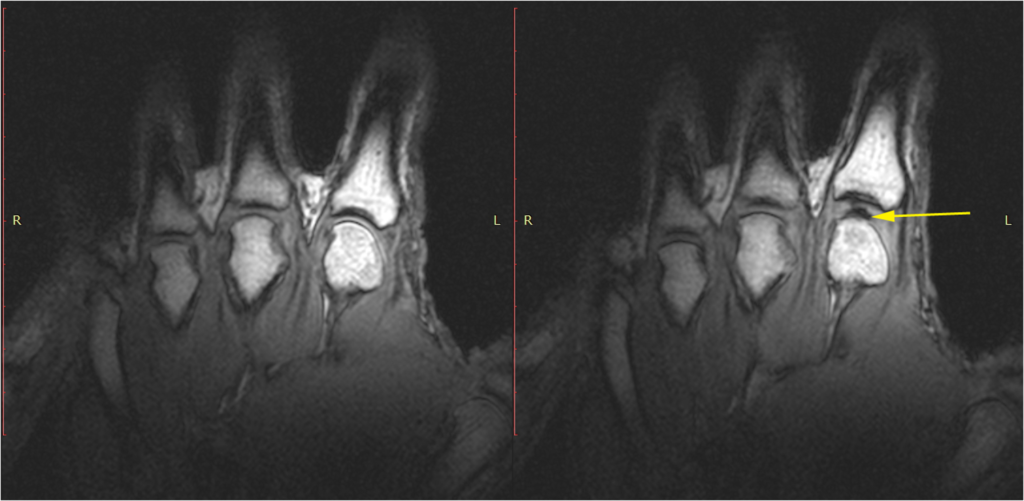

Cracking joints have garnered interest since early 1900. Nevertheless, the real reason behind the cracking sound remain mysterious. In 2015, researchers used MRI to study cracking knuckles in real time. In the study, researchers observed the development of a cavity between the cracked joints. From this, they postulated that the cavity that had formed had produced the sound.

Cavity formation when cracking knuckles, as shown by the yellow arrow (Source: PLOS One)